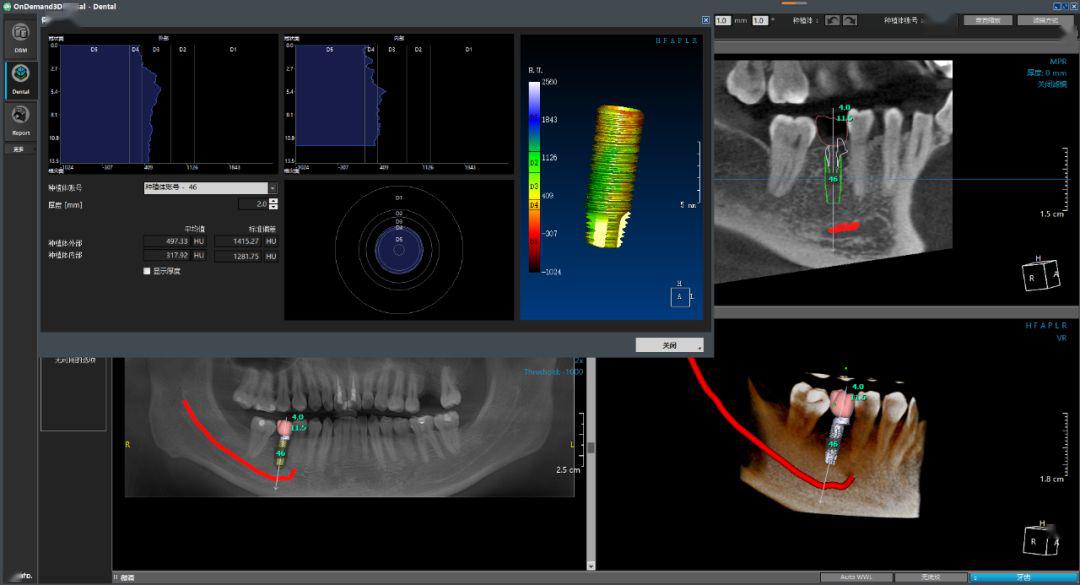

02 种植模拟让手术更便捷

专业软件实现修复为导向的种植模拟,功能与美学两者兼得。

从牙槽骨骨质骨量测量,到根据上下颌咬合关系模拟虚拟牙冠,再到种植体型号选择,最后到种植体基台选择,手术过程全方位设计,降低手术风险,增强医患沟通。

(图:种植体型号超1万多种,色差对比度的骨密度查询)